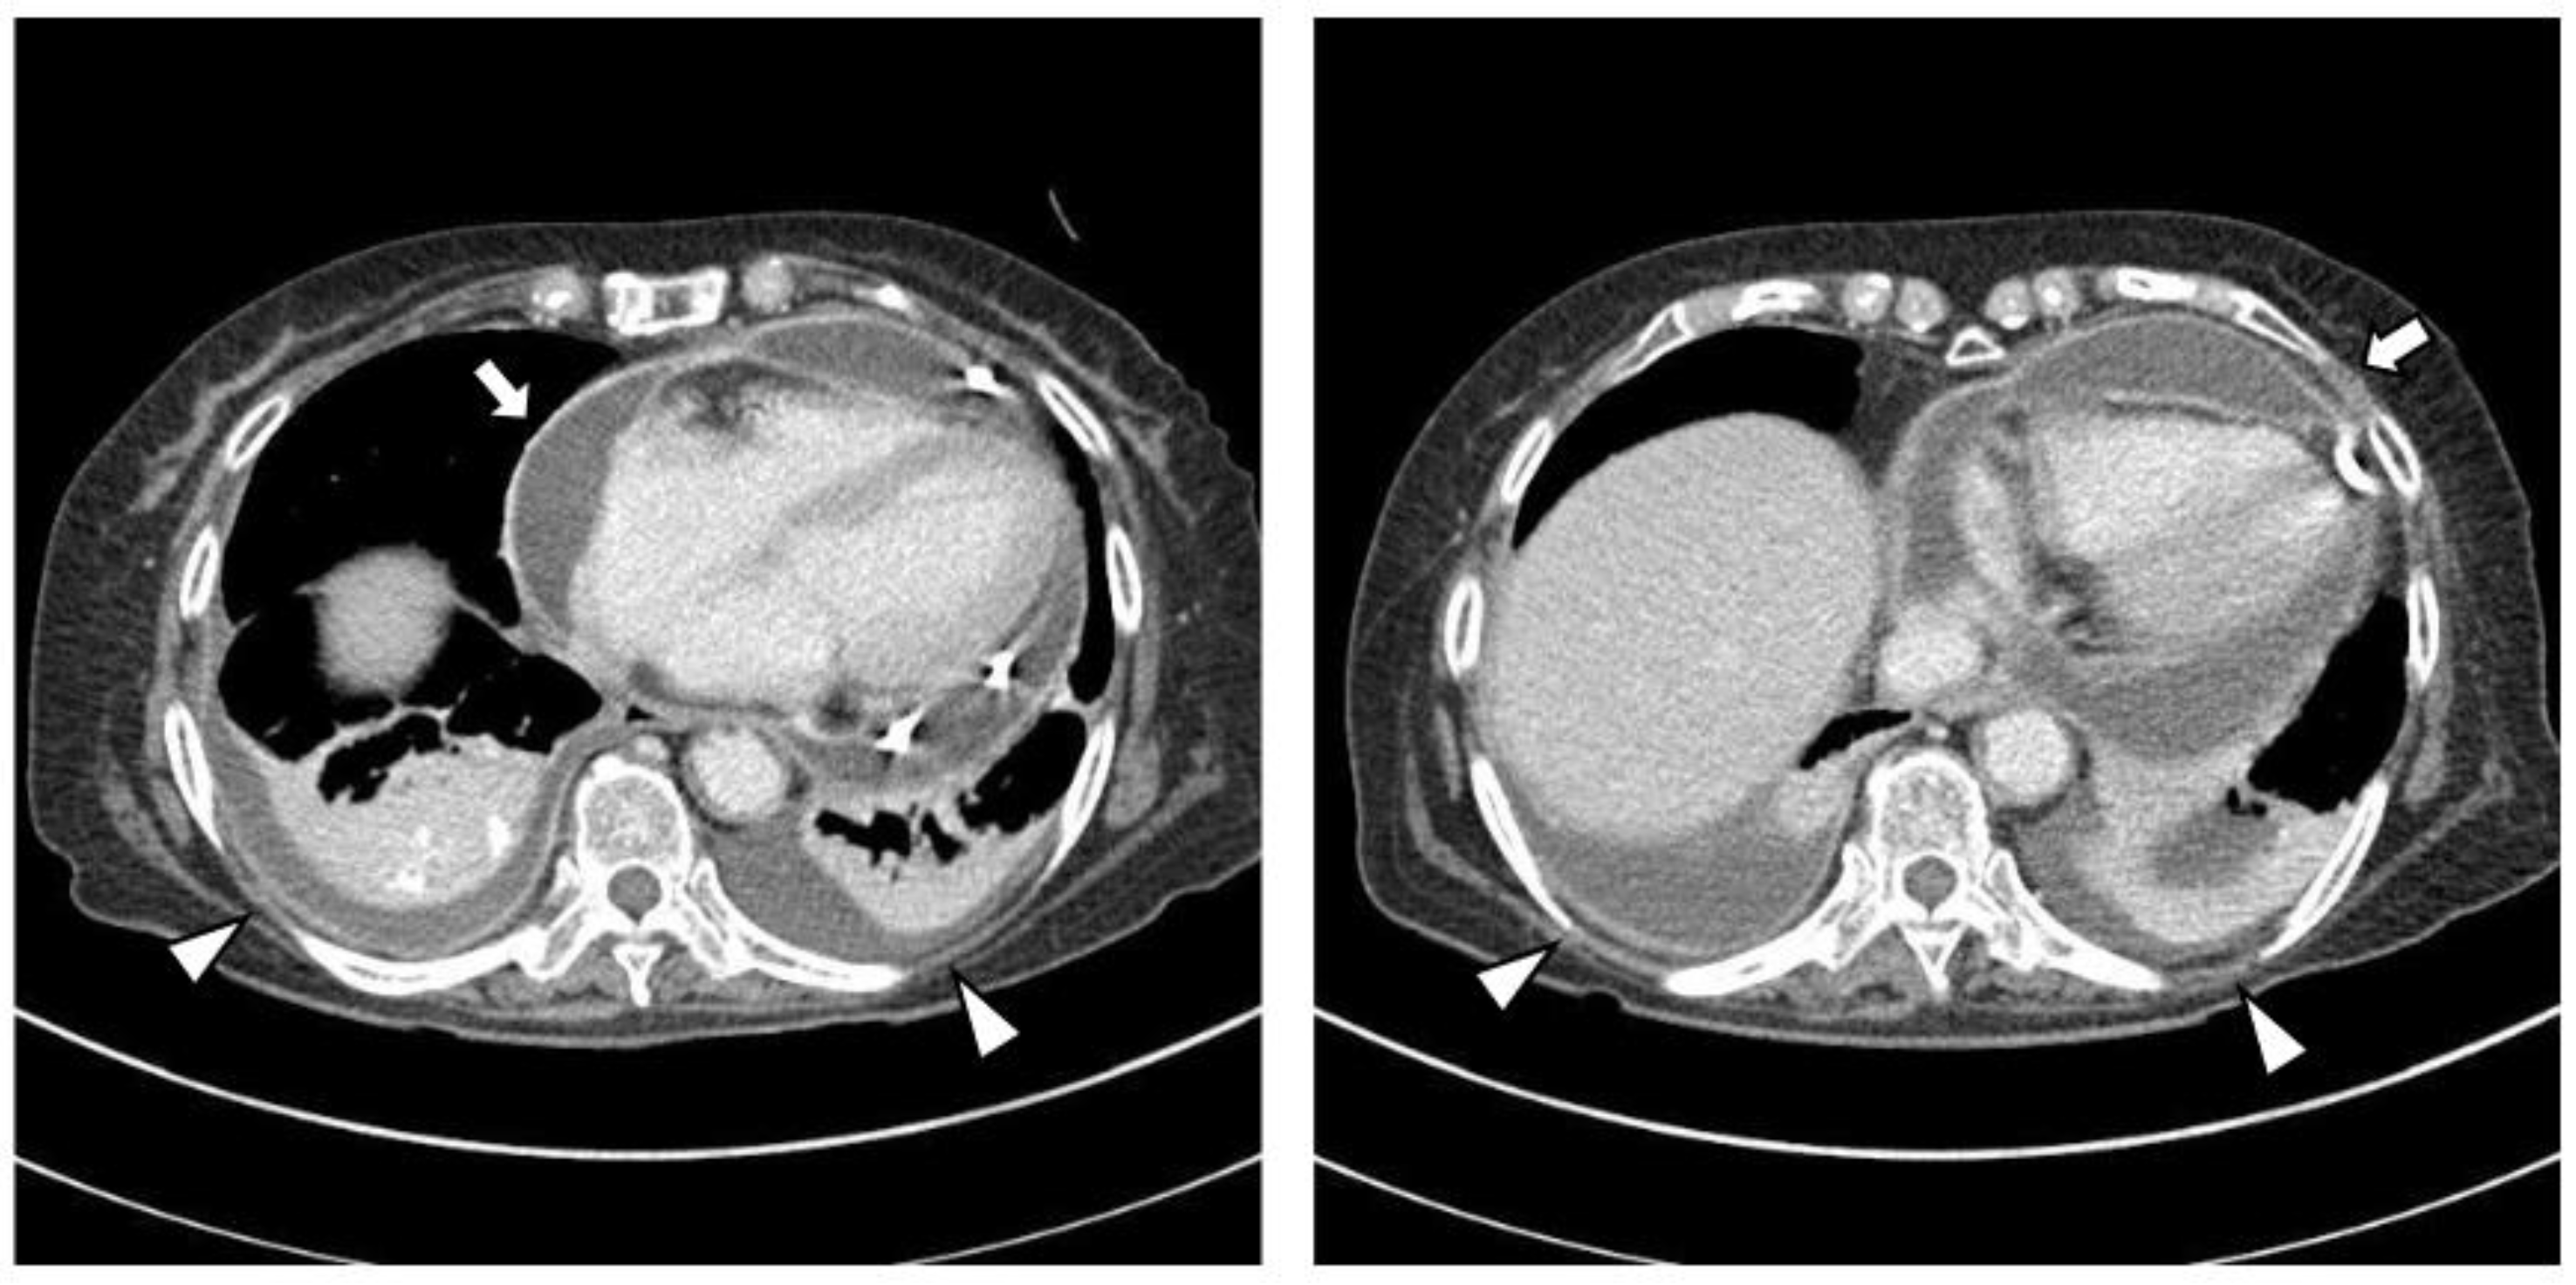

The chest CT showed notable pericardial effusion with pericardial enhancement and pleural effusion with pleural enhancement (Figure 2). The abdominal CT showed fluid collection in both perirenal spaces and diffuse infiltration in both kidneys (Figure 3). Pericardial biopsy revealed chronic active inflammation with nonspecific findings. The PET/CT showed increased uptake in the sacrum, distal femur, proximal tibia, and spleen, with pericardial and pleural effusion (Figure 4). The simple radiography and MRI of the left knee showed patchy sclerotic changes in the medulla of the distal femur and proximal tibia (Figure 1).

Figure 2.

Upon chest computed tomography, there is a large amount of pericardial effusion with pericardial enhancement, which shows a thickened pericardium (white arrows). In addition, there is a moderate amount of pleural effusion and pulmonary edema with pleural enhancement (white arrowheads). There is no definite evidence of a malignant mass or nodule in either side of the lung.